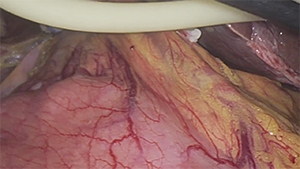

腹腔镜原位解剖性右半肝切除术治疗初始不可切除肝癌

作者:陶海粟 | 作者单位:南方医科大学珠江医院